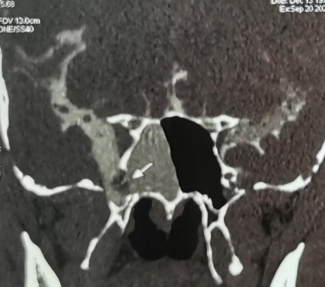

箭头位置为脑脊液鼻漏并发脑膜脑膨出处

通俗地说脑脊液鼻漏,就是颅底与鼻腔鼻窦分隔的骨质和脑膜有破损,颅内的“脑脊液”从破损的地方流到了鼻腔里,形成了水一样的“清鼻涕”。陈女士在发病前未受过外伤,也未做过颅底及鼻窦手术,属于自发性脑脊液鼻漏。